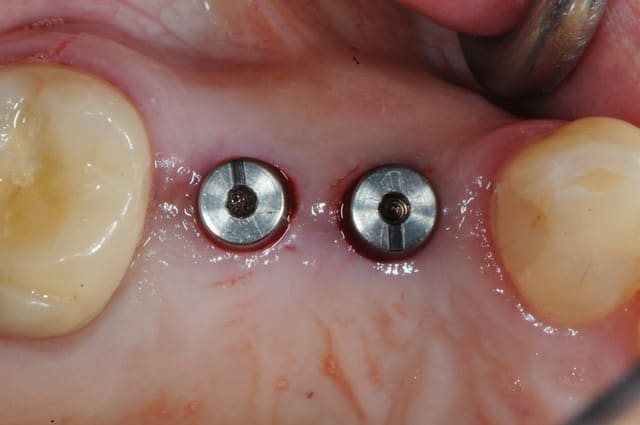

voici le dernier né de la gamme Axiom d'Anthogyr.

il est commercialisé depuis le premier janvier de cette année sauf pour ceux qui ont effectué les essaies cliniques (j'en faisais pas partie--snif!), ceux là pouvaient le commander avant.

il a un corps conique et des spires beaucoup plus agressives pour augmenter la stabilité primaire.

son diamètre au niveau du col est légèrement réduit ce qui limite la compression crestal.

on conserve exactement la même connectique que son grand frère l'Axiom REG donc aucun changement pour la prothèse et bien entendu on conserve aussi le platform switching.

le cas que je vous présente date d'hier, il n'a rien d'extraordinaire, alors soyez indulgents, c'était juste pour le plaisir de partager ça avec vous.